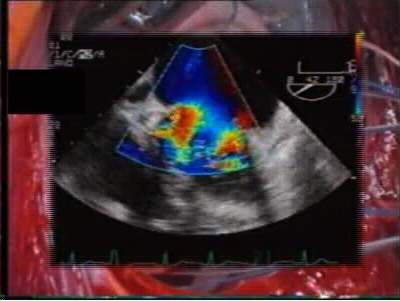

Intraoperative, post-repair TEE is mandatory, as with any other repair technique, to verify the results of the correction. In the specific setting of the edge-to-edge technique, TEE should exclude not only residual regurgitation, but also valve stenosis. Valve area may be assessed by Doppler methods, since flow velocity through the valve is not affected by the type of surgical procedure.4 We mostly rely on planimetric valve area, assessed in the transgastric, short-axis view of the mitral valve. In case of doubts, pressure measurements of the transvalvular gradients may be obtained to exclude mitral stenosis intraoperatively. Mid-term follow-up TEE data showed good results of the repair, with stable competence and no progression of valve stenosis (see chart3). Exercise Doppler-echocardiography may be useful in case of suspicion of mitral stenosis at baseline examination. It must be noted that following double orifice repair, valve area is flow dependent (functional reserve), since it increases during exercise, as for the native mitral valve.5